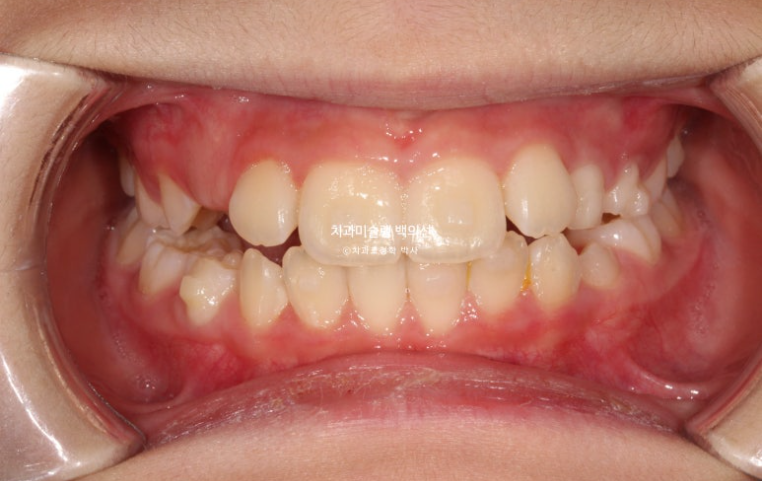

25년 6월 드디어 치료를 마무리 했습니다.

25.06

중심선은 잘 맞습니다.

아직 작은어금니들이 좀 더 내려와야 교합이 안정됩니다.

23.06~25.06

남아있는 유치는 없고 완전한 영구치열에 접어들었습니다.

나중에 2차교정을 안해도 될 정도가 되었습니다.

좋은 결과를 오래 유지하기 위해서 철사 고정식 유지장치 및 가철식 유지장치까지 꼼꼼하게 들어갑니다.

총 치료기간은 2년이고 중간에 쉬는 기간은 5개월이었습니다.